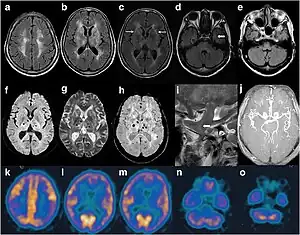

MRI of a person with FFI showing abnormal signals in the frontoparietal subcortical areas. MRA showed smaller distal branches of cerebral arteries.